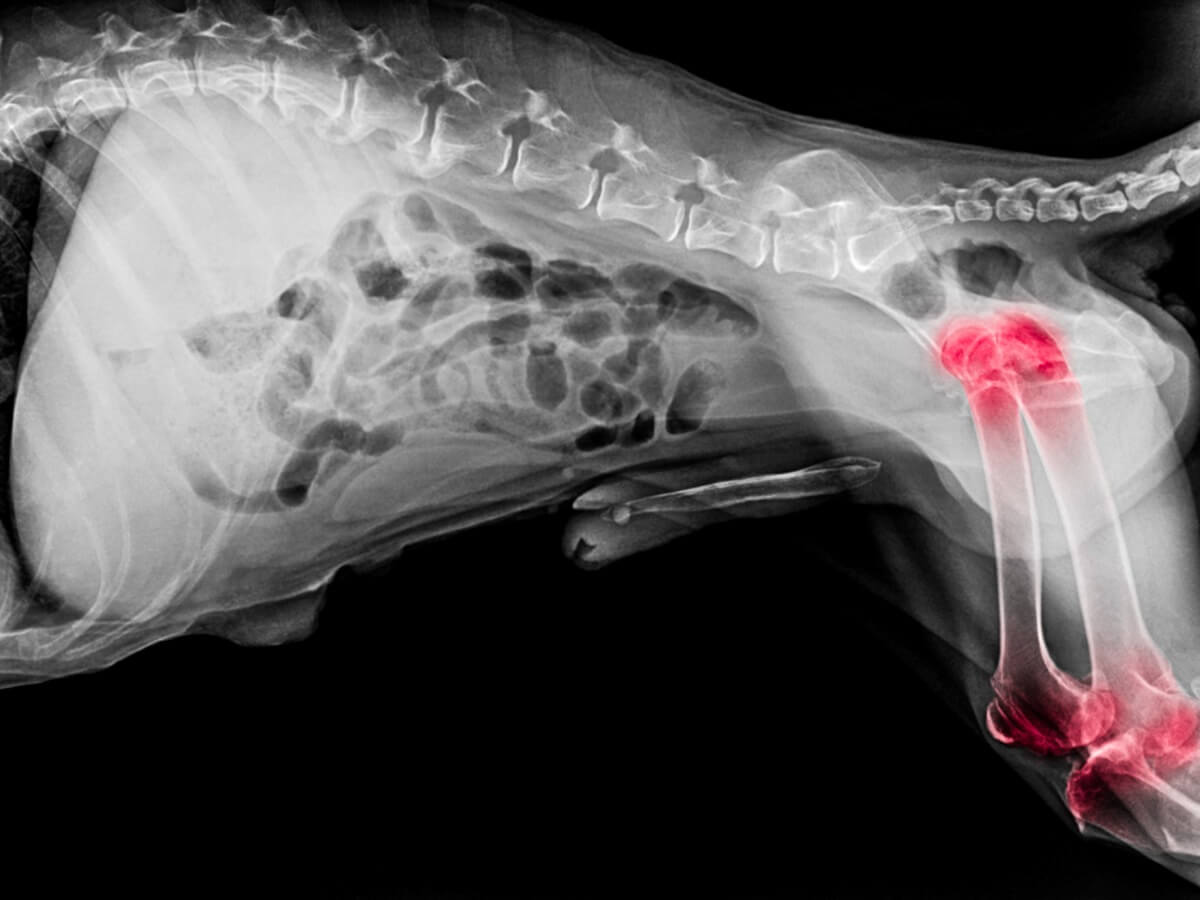

Artrit och artros är mycket vanliga sjukdomar hos hundar, slitage på lederna leder ofta till en av dessa två sjukdomar. Även om symtomen kan verka lika så är orsakerna och konsekvenserna av var och en olika. Att lära sig att skilja mellan de två hjälper ägaren att bättre förstå vad deras husdjur går igenom.

Som nämnts kan artrit och artros uppvisa en serie liknande symptom, men sjukdomarnas ursprung är olika. I var och ett av tillstånden påverkas en annan struktur av leden. Vid artrit föreligger inflammation i ledhinnan, medan artros beror på problem med brosket.

Artros är ett annat tillstånd än artrit, det kännetecknas av den progressiva förlusten av brosk. När sjukdomen fortskrider tappar hunden helt sin rörlighet i det drabbade området. ”Stötdämparen” mellan de två benen finns inte längre. Artros kan orsakas av ett antal faktorer, inklusive följande:

Symtom på artrit och artros hos hundar

Dessa sjukdomar har liknande symptom eftersom de båda påverkar lederna. Följande lista sammanställer de mest uppenbara tecknen hos hundar som kan indikera förekomst av artrit eller artros.